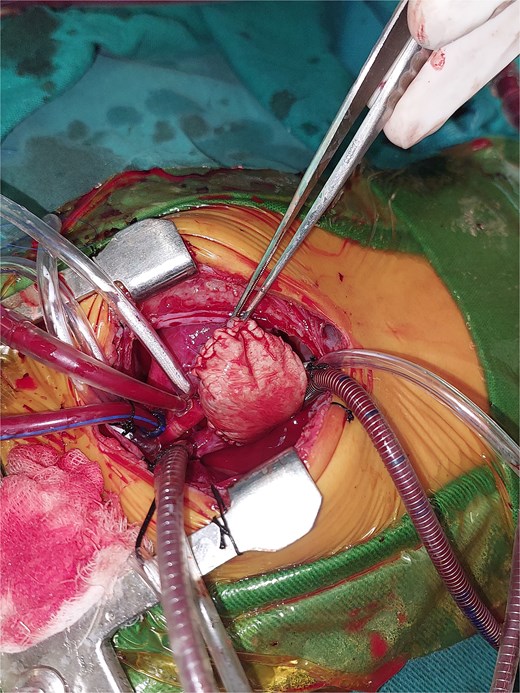

A 2-month-old female infant was admitted with respiratory distress characterized by tachypnea, and cough, along with poor feeding and systemic symptoms such as fever and episodic diaphoresis. At 25 days of age, she had previously been hospitalized for similar symptoms, during which a massive pericardial effusion was identified. Initially, an extracardiac mass was suspected. Despite undergoing two pericardiocenteses and resuscitation after two post-cardiac arrest events, her clinical status continued to deteriorate, and she was referred for urgent surgical intervention due to cardiogenic shock from pericardial tamponade. On examination, she appeared pale with respiratory distress, intercostal retractions, pulsatile hepatomegaly (2 cm), splenomegaly (1 cm), and tachycardia (160 bpm). Laboratory findings showed hyponatremia (125 mmol/L). TTE demonstrated cardiomegaly, bilateral pleural effusion, and a massive pericardial effusion measuring 24–28 mm circumferentially. A 2.7 cm mass adjacent to the anterior RA wall and atrioventricular (AV) groove was identified (Fig. 1). Due to her unstable condition, CT imaging was deferred. An emergent median sternotomy revealed a severely distended pericardium containing copious effusion (Fig. 2). Upon opening the pericardium, immediate hemodynamic improvement was observed. The mass was visualized infiltrating the RA anterior wall and AV groove (Fig. 3). Total cardiopulmonary bypass (CPB) was initiated using aortic and bicaval cannulation. Following cardiac arrest with antegrade cold blood cardioplegia, the RA was incised posterior to the tumour. The lesion extended beyond the AV groove, precluding complete excision due to anatomical constraints (Fig. 4). Subtotal (debulking) resection was performed (Figs 4 and 5), and the RA anterior wall was reconstructed with a bovine pericardial patch (Fig. 6). The patient was successfully weaned from CPB, and the remainder of the surgery was uneventful. The infant was extubated within 48 hours and discharged after a 14-day hospital stay, with subsequent TTE showing satisfactory cardiac function. Histopathological evaluation confirmed a benign capillary hemangioma characterized by lobulated reddish tissue with compact capillary proliferation, fibrous septae, and stromal hyalinization. Immunohistochemical staining was positive for CD31 and CD34, confirming endothelial origin and ruling out malignancy (Fig. 7). At one-year follow-up, the patient remained in excellent general health with no signs of recurrence.

Intraoperative image showing the mass in the right atrium after opening the pericardium.